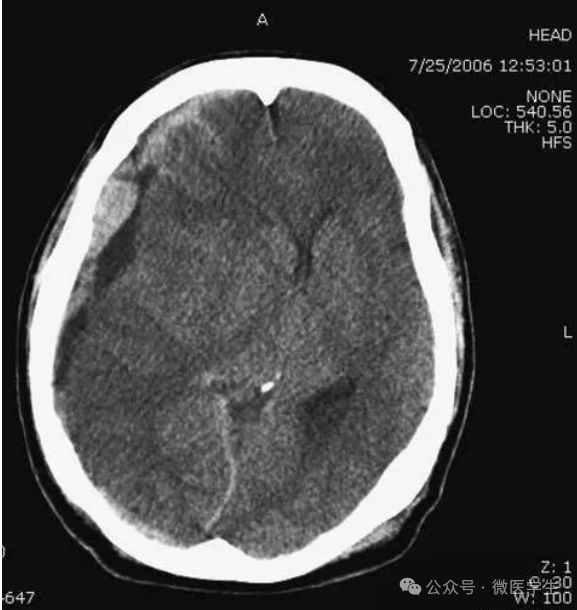

头部枪伤:

可见子弹轨迹,穿越大脑中线,

其毁灭性后果导致:

侧脑室积血,蛛网膜下腔出血,

脑积水(侧脑室颞角扩大),

小脑幕疝(脑干周围基底池消失或不对称)。